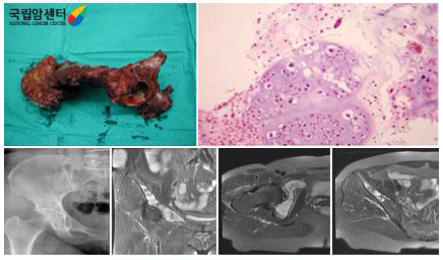

혈액검사, 방사선검사, 핵의학검사(골 스캔), 자기공명영상(MRI)으로 진단하며 원발성, 전이성 골종양 및 골결핵을 포함한 감염성 질환들을 감별해야 하며, 조직검사로 확진합니다.

원발성 골종양의 경우 원인을 모르는 뼈의 통증이 계속되고 종괴가 만져질 경우 혈액검사, 방사선검사, 핵의학검사(뼈 스캔), 자기공명영상(MRI)으로 진단하며 조직검사로 확진합니다.

근골격계 병변의 평가에 있어 중요한 방사선 검사로 특히 종양의 진행단계를 결정하는데 필수적인 검사입니다. 조직간의 구분이 명확하고 여러 각도에서 촬영이 용이하여 골종양의 크기나 모양, 주위 조직과의 관계, 혈관이나 신경과의 관계를 잘 알 수 있습니다. 또한 종양의 침범 범위가 될 수 있는 근육, 피하 지방, 관절, 신경 혈관 구조물 등에 대해 정확한 정보를 주므로 사지 구제술(보존술)의 적용 가능성 판정과 절단 시의 절단 범위 결정에 절대적으로 자기공명영상(MRI)검사가 필요합니다. 종양에 대한 항암화학요법 전후에 영상을 비교해 치료 효과 판정에 이용하기도 합니다.

[ 악성 골종양의 자기 공명영상 사진 ]

정확한 진단을 위해서는 조직검사가 필수적이며, 조직검사에는 천자검사법, 침 생검법과 수술을 하는 절개 생검법이 있습니다. 방사선검사나 자기공명영상(MRI)으로 어느 정도 예측은 가능하나 악성 골종양의 확실한 조직학적 진단을 위해서는 조직검사가 필요한 경우가 많습니다. 필요한 모든 다른 검사 후 진단의 최종 단계에 시행되는데, 이는 조직검사로 인해 종양 주위에 출혈이나 염증 등이 야기될 수 있어 방사선검사, 특히 자기공명영상(MRI) 검사에 지장을 주기 때문입니다. 조직검사의 방법과 위치는 나중에 시행될 사지 보존을 위한 수술적 치료를 생각하여 골종양 전문의에 의해 시행되어야 합니다.